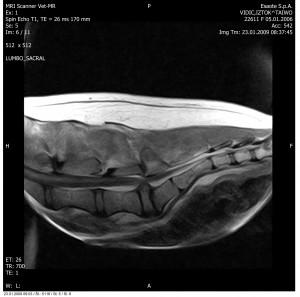

Slika: Primer vnetega medvretenčnega diska